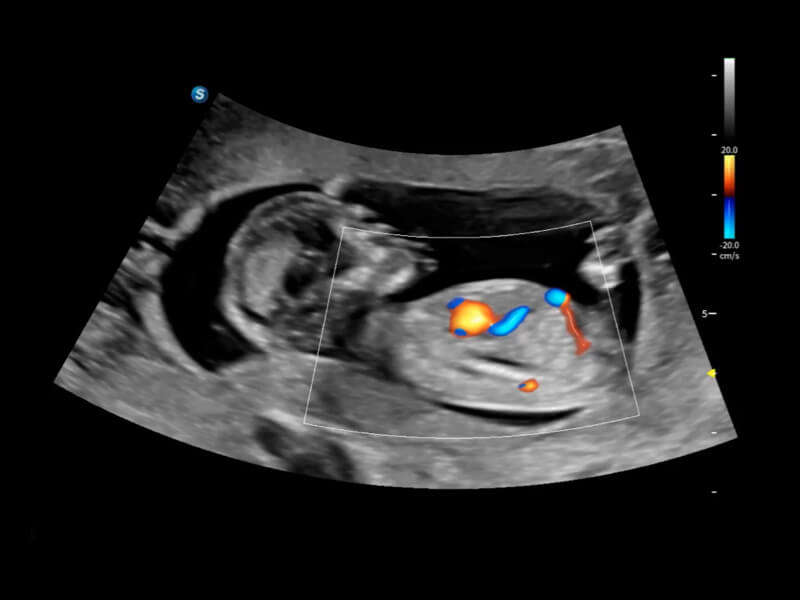

丰富的血流动力学检测技术,可在不同医疗场景中高效捕捉血流信号,助力临床诊疗。

在传统血流的基础上优化扫查和算法策略,能够更好的抑制组织信息,提炼红细胞运动信息,得到更高帧频,高灵敏度和分辨率的血流信号,还原更真实的血流动力学。

通过光照模型,使二维血流显示出立体的效果,增加血流的敏感性、成束性,减少外溢。可以和其他不同的血流技术联合使用,融合不同技术的优势。轻松应对微小血管,增强血流的立体效果,提升视觉敏感性。

通过创新的Matrix E自适应滤波算法,能有效滤除软组织和噪声信号,最大限度保留超低速微细血流的信号;结合超长时间域算法,极大提升细微血流的敏感性和空间分辨率,更真实的反应组织、包块的血流灌注情况。